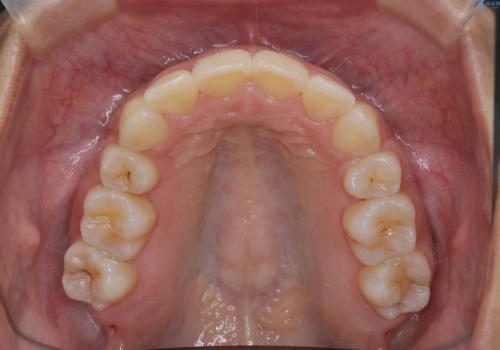

- 前歯の凸凹を主訴に来院されました。

抜歯を行い、ワイヤー矯正にて治療を行いました。

凸凹もなくなり、歯磨きもしやすくなったと喜んでいただきました。

CTにて骨を確認し、側切歯の歯根をこれ以上頬側に出せないことを確認しています。